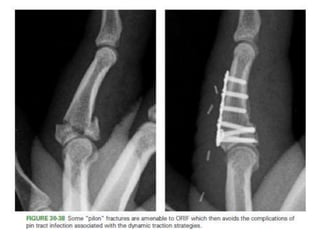

• Pilon fractures.

– Highly unstable,stifness of PIPJ.

– Dynamic traction / dorsal spring mechanism.

– The general principle is to establish a foundation at the center

of rotation in the head of P1.

– traction (adjustable or elastic) is applied along the axis of P2

to hold the metaphyseal component of the fracture out to

length

– while allowing early motion to remodel the articular surface

• Temporary TransarticularPinning for Partial Articular Base Fractures. • Volar Base Fractures – CRIF /ORIF • Pilon fractures. – Highly unstable,stifness of PIPJ. – Dynamic traction / dorsal spring mechanism. – The general principle is to establish a foundation at the center of rotation in the head of P1. – traction (adjustable or elastic) is applied along the axis of P2 to hold the metaphyseal component of the fracture out to length – while allowing early motion to remodel the articular surface